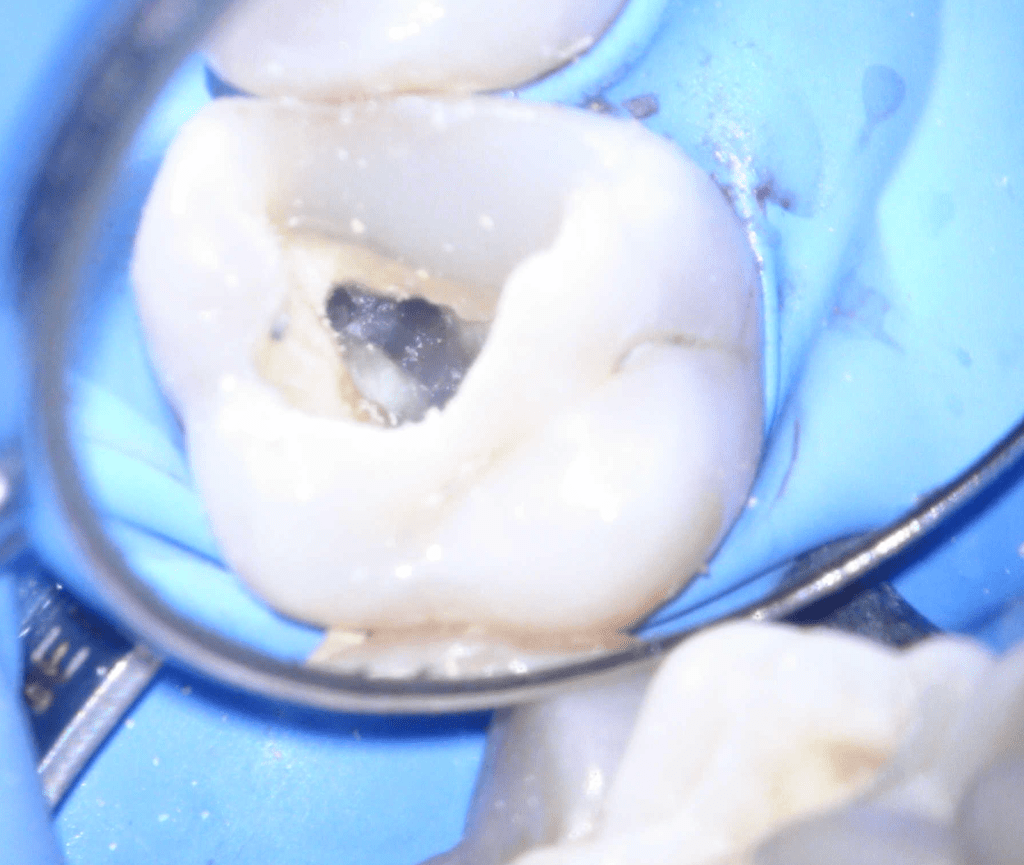

Fisura, remoción amalgama para explorar